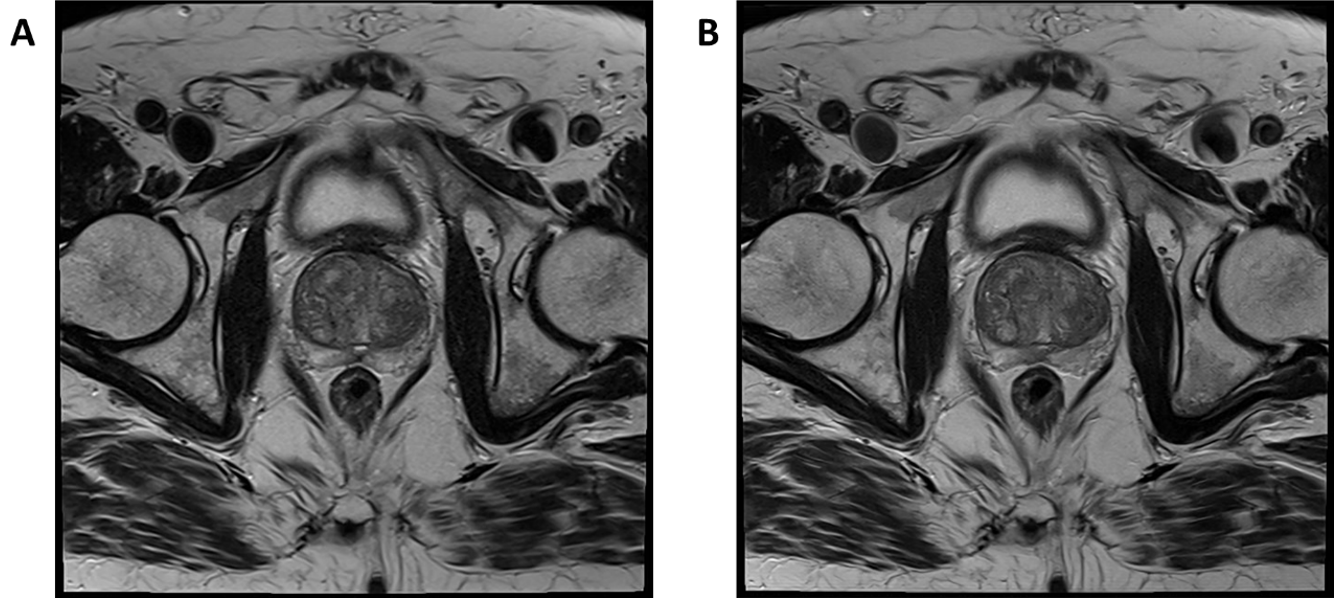

Case study 3: Deep Resolve Boost in prostate imaging on Siemens Sola (XA51)

Dr Matthew Birkbeck, Newcastle upon Tyne NHS Foundation Trust